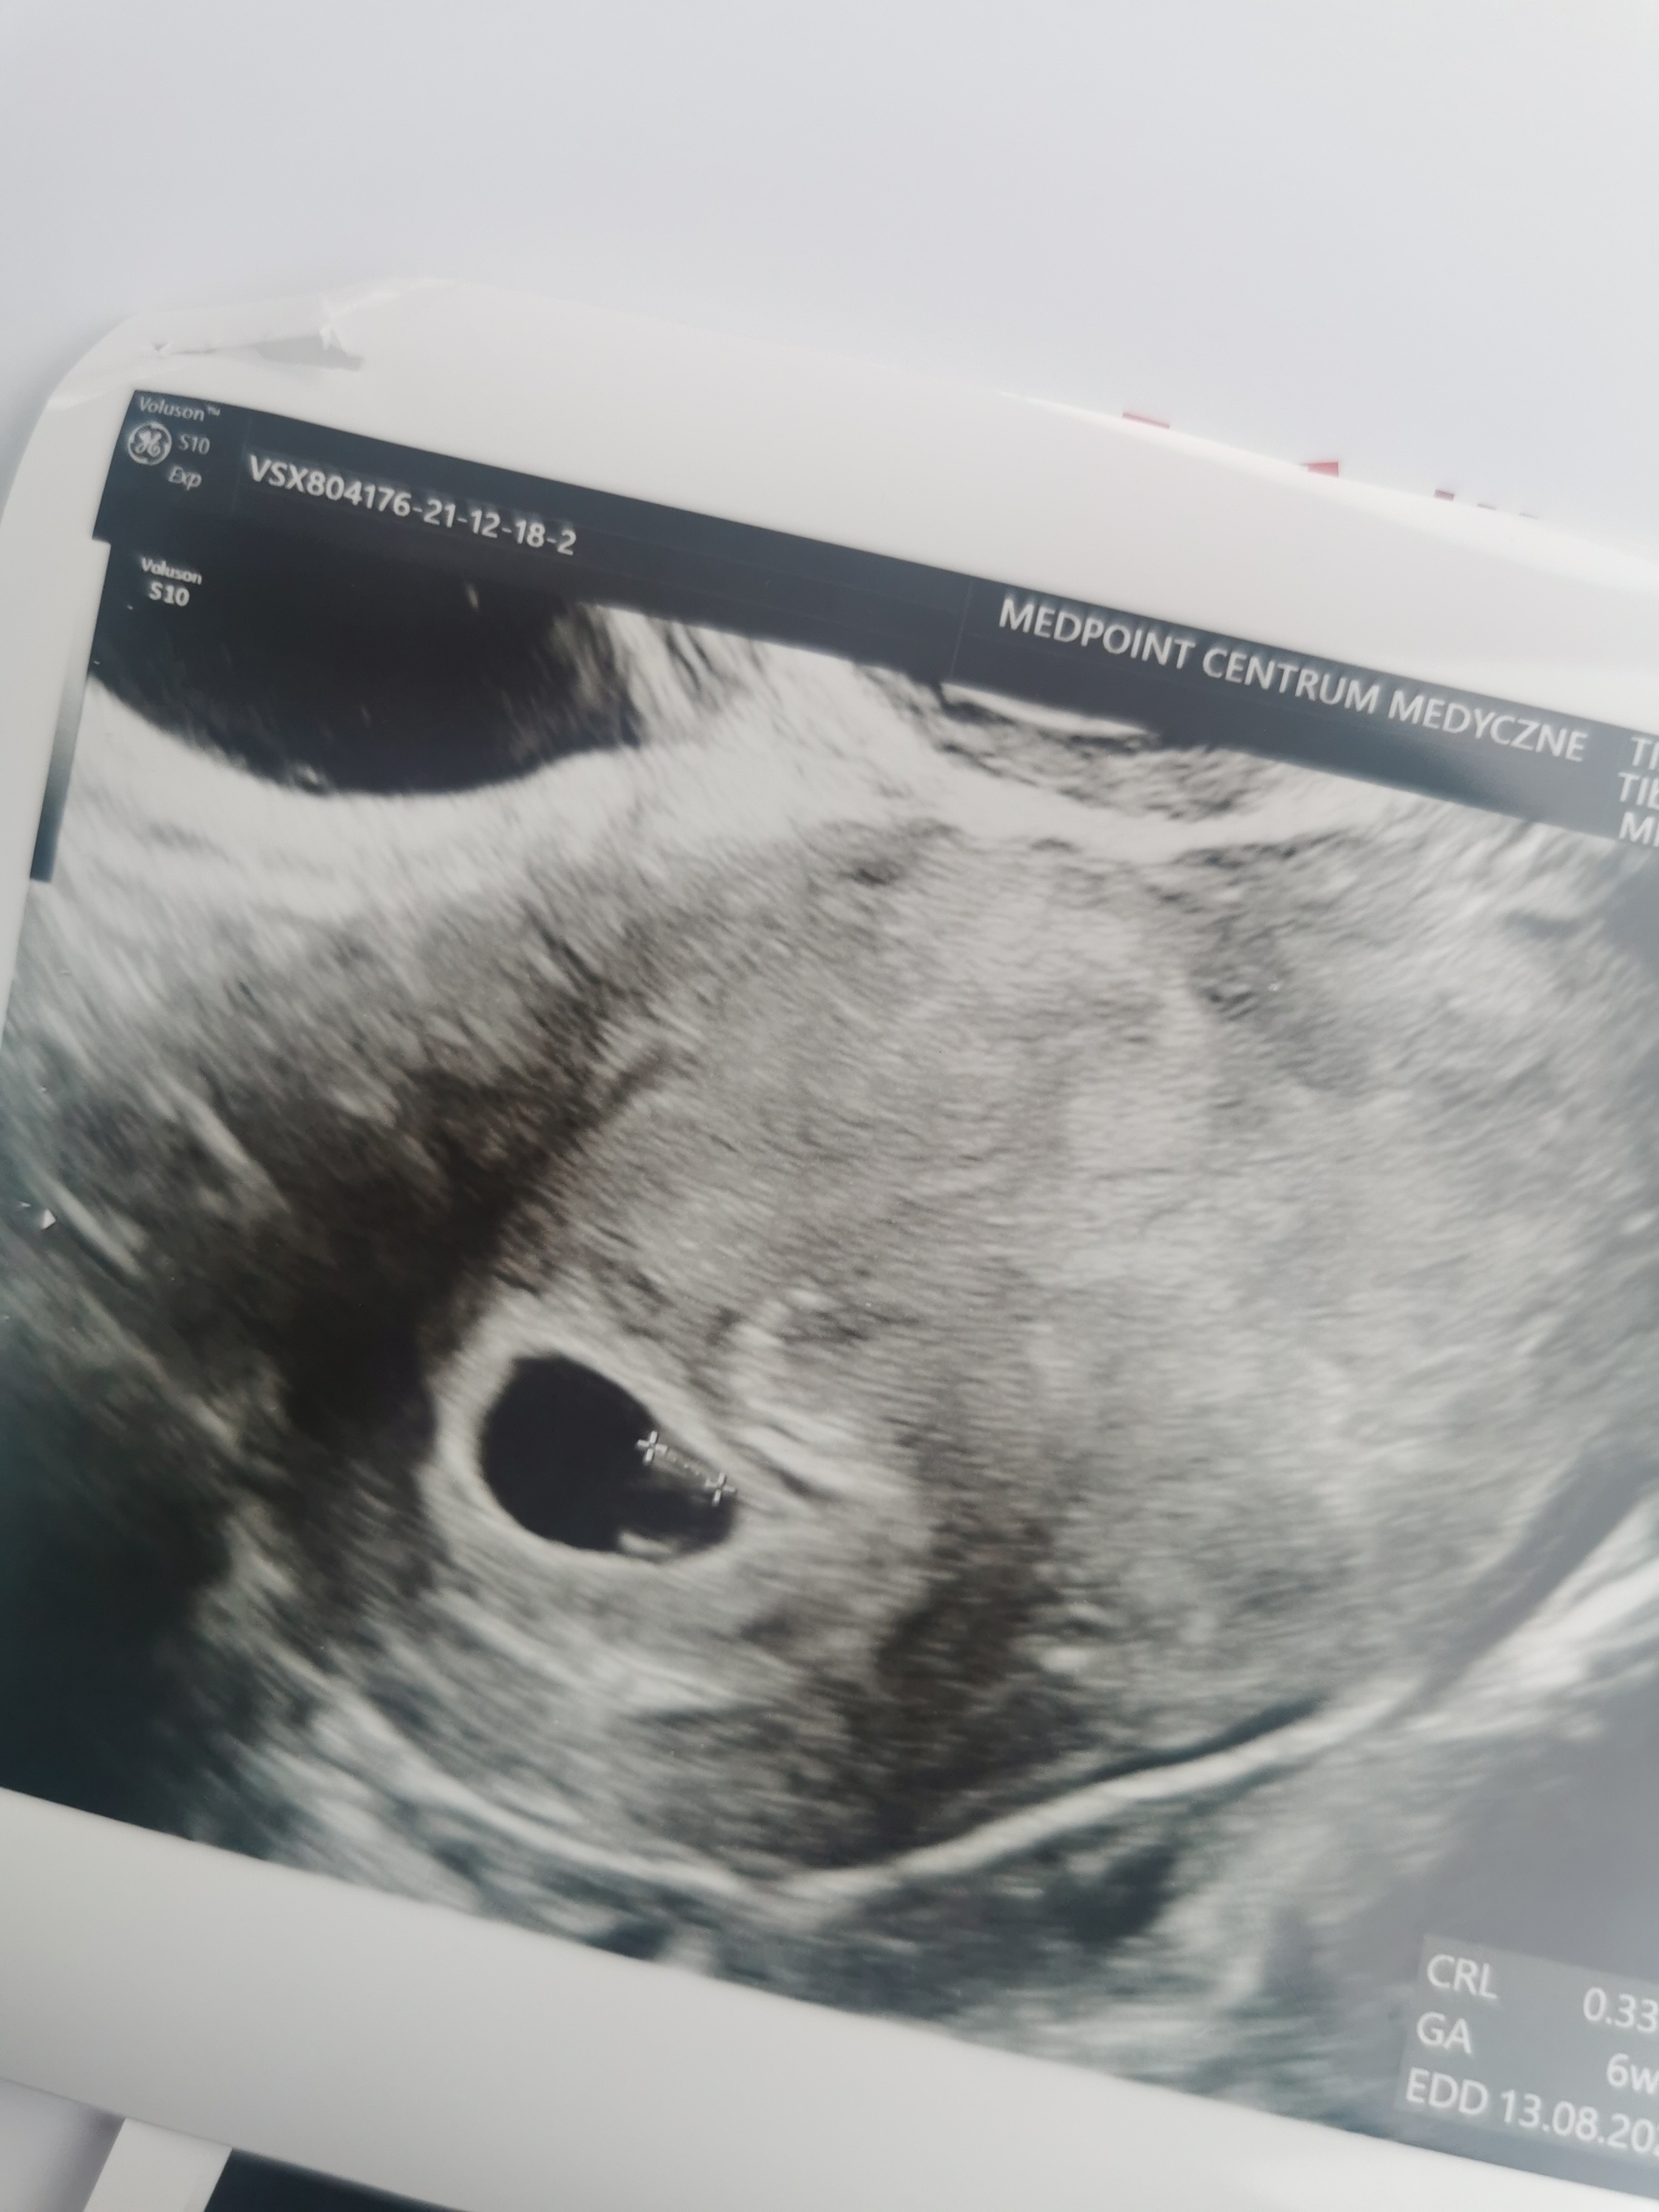

Hej dziewczyny.bylam wczoraj na usg. Mam wyliczone dokladnie 6 tyg wczoraj i mamy pecherzyk 1.1,cialko zolte i zarodek 3.3 z zaczynajacymi sie tlic komorkami i to bylo wlasnie tworzace sie serduszko . Dziękuję za Wasze wsparcie♥️ jedyny problem to maly krwiak 1.7x1, ale nie przylega do pęcherzyka i jest dość jasny na obrazir wiec prawdopodobnie sie wchlania. Odpoczywam i czekam na Dzidzie♥️

Załączniki

• IMG_20211218_133342.jpg

IMG_20211218_133342.jpg

957,7 KB · Wyświetleń: 117

• IMG_20211218_133252.jpg

IMG_20211218_133252.jpg

945,1 KB · Wyświetleń: 116